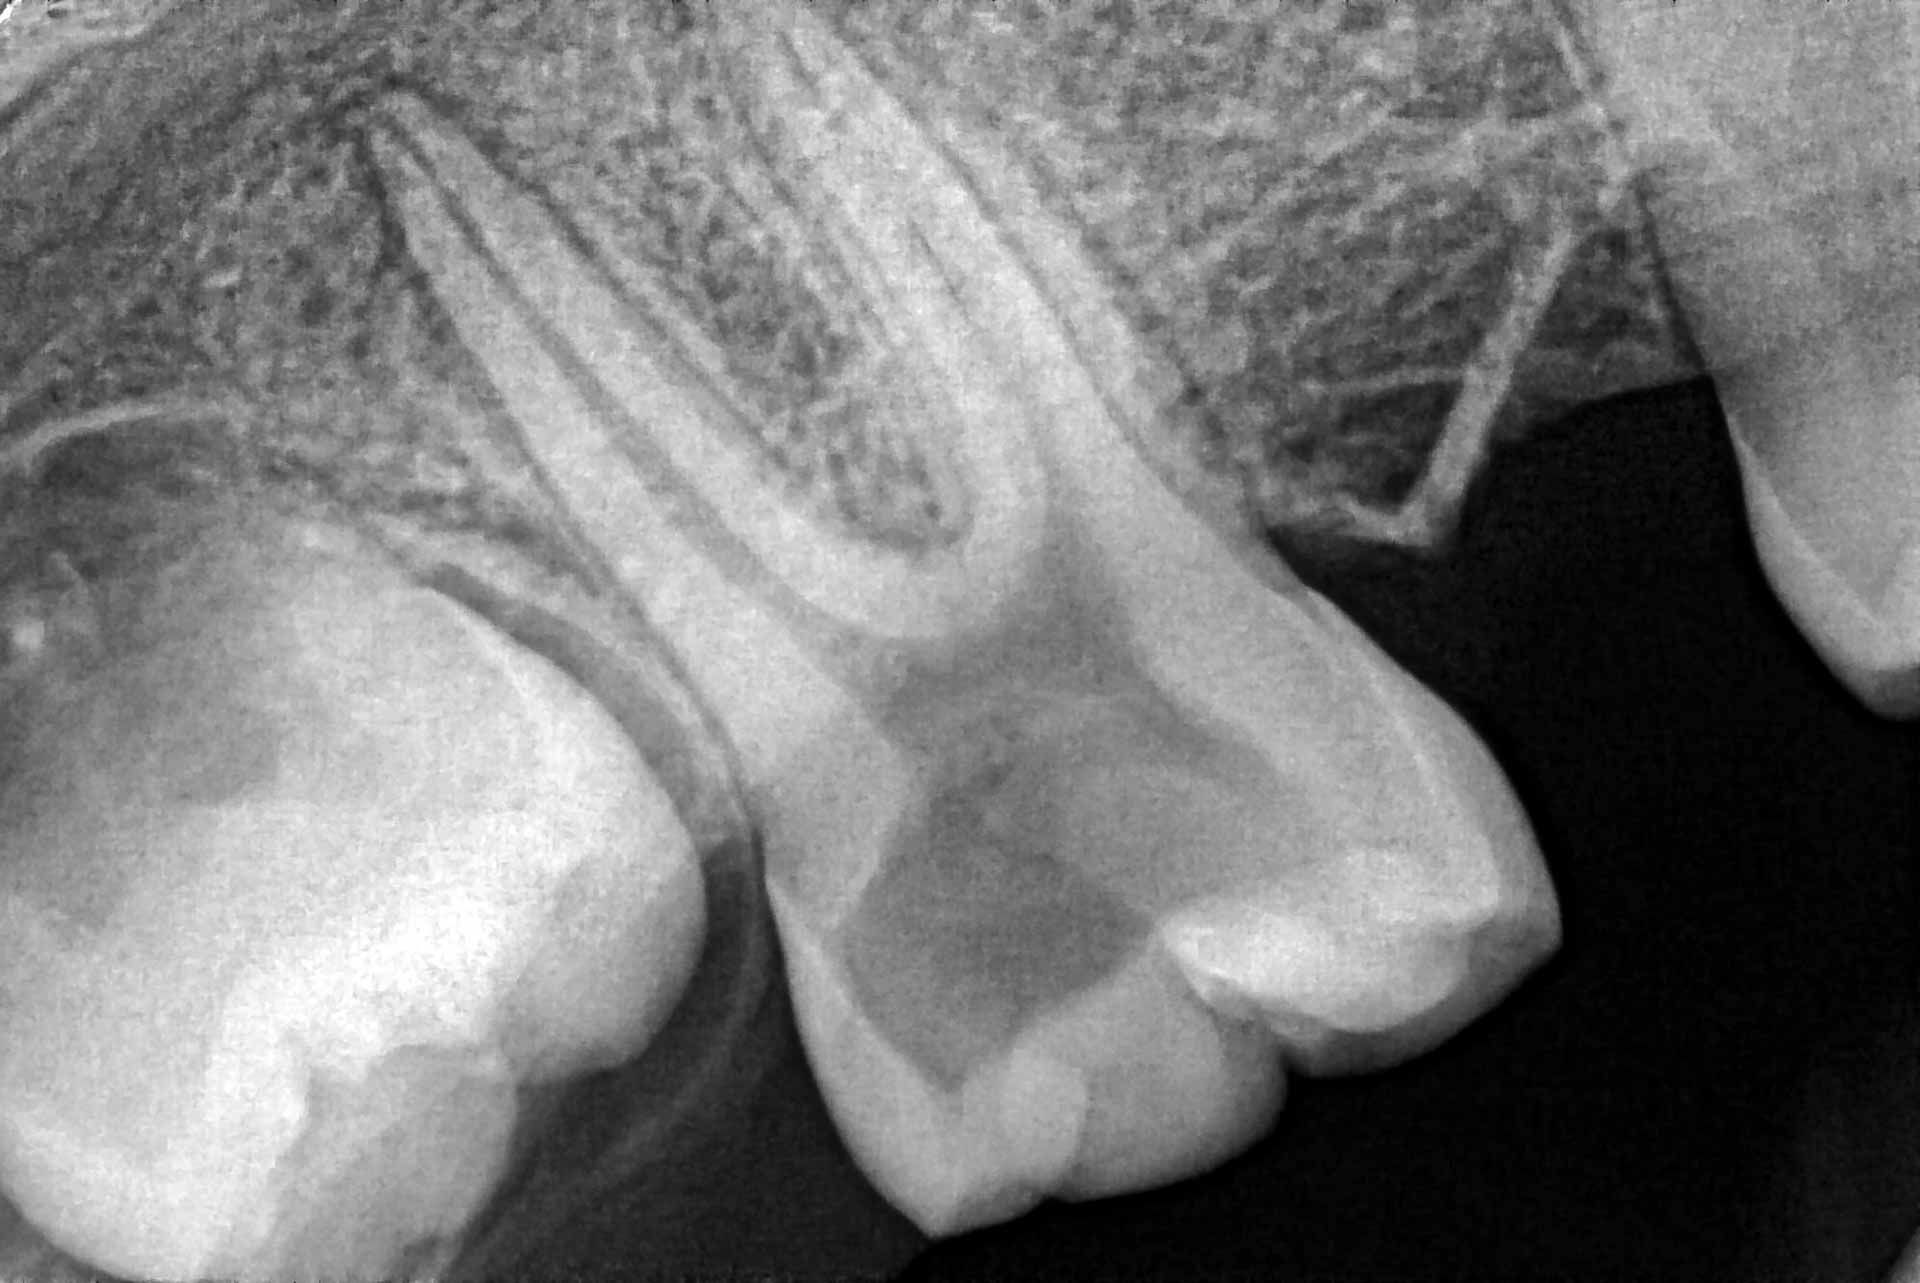

At Omni Endodontics, our board-certified Arlington root canal dentists use advanced technology, including 3D CBCT imaging, laser-assisted cleaning, and microsurgical tools, to deliver root canal care that is precise, gentle, and efficient.

- We’ll take 3D CBCT scans to clearly understand the source of your discomfort and create a precise treatment plan.